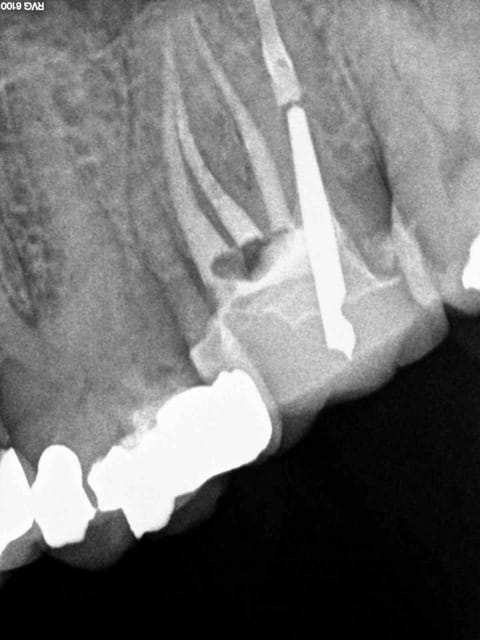

Le mv1 et le dv ont été obturés il y a 8 ans en mono cone.

En gutta chaude la différence se voit car ca n'est pas homogène à la radio comparé à un monocone scellé.

Marc vas jouer du mac spadden sur le canal palatin si ca te chante, mais pas sur moi ! -)))

4 wgbx1x - Eugenol

3 b4nxvh - Eugenol

1 phwbbp - Eugenol